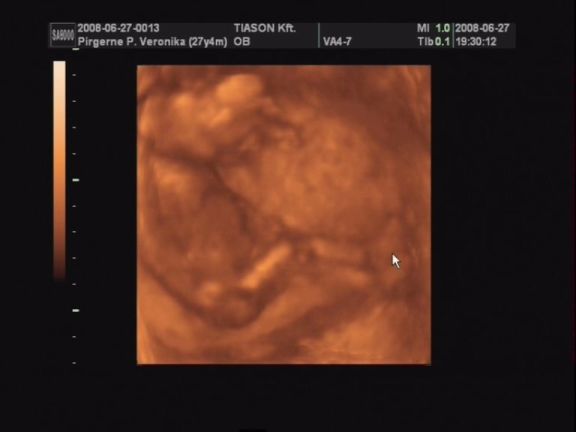

Csodálatos élmény volt az uh!

Nem lehetett még látni, kisfiú vagy kislány van odabent, de nagyon nagyon jó lett a videó. Rengeteget mozgott, rugdalózott, kitámasztotta magát, kalimpált a kezével, iszonyú jó volt. Még a pofijáról is van kép, az is egészen jól látszik.

Egyszóval nagy a boldogságunk, gondolhatjátok. :lol:

Próbálok majd egy két képet levarázsolni a videóról és felrakni hétvégén.